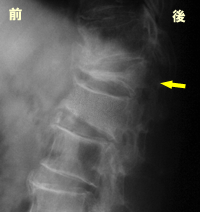

偽関節

場合によっては、骨折部がくっつかず

不安定な状態(偽関節)になることもあ

ります。右の写真では矢印の部分が偽

関節です。立位では臥位に比べて椎体

の前方が潰れて見えます。